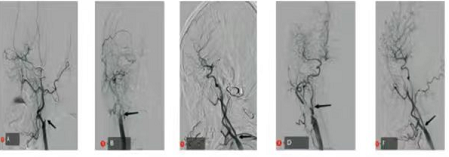

科室开展的急诊脑动脉取栓术及同期合并颈动脉支架成形术,如下图所示:

A图为取栓术前侧位见颈内动脉近端塞

B图为取栓术前正位见颈内动脉近端未见显影

C图为取栓术后见颈内动脉起始段极重度狭窄、正向血流难以维持

D图颈动脉支架植入术后正位见颈内动脉正向血流前交通开放

F图为颈动脉支架植入术后侧位脑血流明显改善